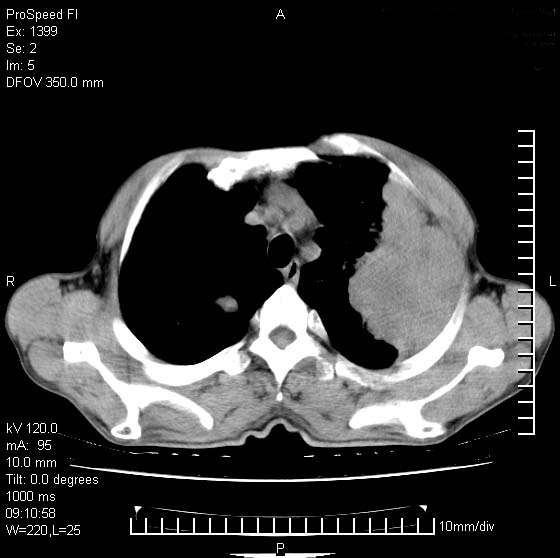

以下是引用卜一在2007-1-19 9:55:00的发言:[br]左肺沿胸膜下巨大肿块影,边缘呈分叶征,纵隔内见肿大淋巴结,右肺内另见一不规则结节影 .考虑:左肺周围性肺癌伴纵隔 右肺内转移.

以下是引用rgsyyf在2007-1-19 11:05:00的发言:[br]左肺上叶见形态不规则巨大软组织肿块影,边缘呈分叶征,纵隔内隆突下见肿大淋巴结,右肺内另见一不规则结节影 .考虑:左肺周围性肺癌伴纵隔即右肺内转移.